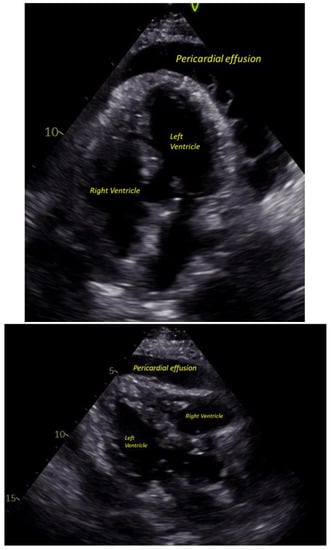

On presentation, she looked clammy, she was afebrile (T 36.8 °C), tachycardiac (HR 107) and tachypneic (Respiry Rate 26), yet normotensive (Blood pressure 104/80), and she was saturating 100% on room air. The patient had mild hyponatremia, leukocytosis and thrombocytosis, elevated ferritin level, C-reactive protein (CRP) and Erythrocyte sedimentation rate (ESR), and elevated procalcitonin with negative high-sensitivity troponins. Her HbA1C was 7 on admission. An electrocardiogram (EKG) demonstrated sinus tachycardia with diffuse ST elevation with PR depressions with subtle electrical alternans noted (Figure 1). A bedside echocardiogram revealed a large circumferential pericardial effusion with signs of tamponade, most notably early right ventricular diastolic collapse (Figure 2). Our patient was referred for urgent pericardiocentesis with the removal of 450 cc of cloudy yellow fluid. Pericardial fluid analysis demonstrated a neutrophilic leukocytosis. She was empirically started on Piperacillin-Tazobactam and vancomycin for 2 days; culture from pericardial effusion showed pan-sensitive E. coli.

Figure 2. Pericardial effusion on ECHO.